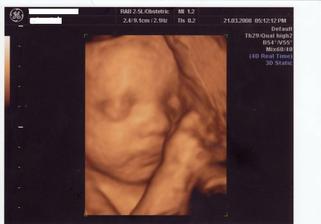

21.3. 3D UTZ v Gennetu byl nezapomenutelným zážitkem a ty peníze za to určitě stojí. Asi půlhodinový utz, kde jsme viděli naší princeznu. Nejdříve měla obličej přikrytý rukama i nohama, ale pak se ukázala - usmívala se, zívala, polykala plodovku. Jen pohlaví nám moc odhalit nechtěla. Stydlivka.